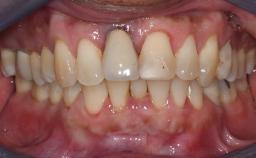

Missing Maxillary Central Incisor, Single Implant Replacement with Adjacent Tooth Restoration

The patient presented with a failing tooth-supported fixed dental prosthesis with cantilever extension replacing the right maxillary central incisor. His chief presenting complaint was poor esthetics, in particular the dark discolored margin around the abutment tooth, the maxillary left central incisor. He reported a history of trauma at a young age, which necessitated the replacement of his maxillary right central incisor as well as root canal therapy of the adjacent left central incisor. The existing prosthesis had been in situ for over 20 years. The initial periapical radiograph displayed good proximal bone levels at the adjacent teeth and a wide incisive canal, which was a concern. The left central incisor presented a very wide root canal treatment with compromised radicular dentin thickness, which was a consideration in the decision between a new tooth-supported fixed dental prosthesis vs. an implant-supported prosthesis. After a lengthy discussion on the risks and benefits of both treatment options, the patient decided on a single-tooth implant replacement.

Esthetic Risk High